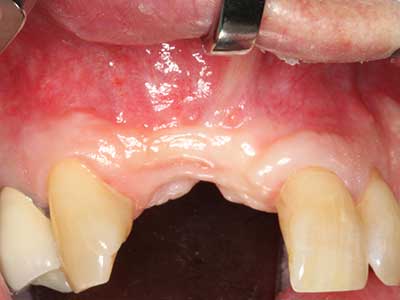

Индикация: Костно разделяне/ шиниране?

Костната тъкан е не само минерализирана структура, тя съдържа и съществено количество колагенови влакна. Това означава, че тя има не само добра компресивна сила, но и известна степен на гъвкавост, която може да се възприеме като предимство при извършване на костна аугментация. В класическата процедура по разширяване чрез костно разделяне, атрофиралият алвеоларен гребен е разделен надлъжно и внимателно разширен след достигане на подходящата остеотомна дълбочина (Фиг. 13-16), в идеалния случай без допълнително отстраняване на периостеума (Brugnami, Caiazzo et al. 2014, Stricker, Fleiner et al. 2014). Системите с винт и пластини с увеличаване на разстоянието при разширяване са доказали ефективността си при разделяне на двете костни ламели, оставайки под прага на фрактурите. В общи линии, оставащата ширина на костта от поне 3–4 mm е задължителна (Chiapasco, Zaniboni et al. 2006), за да се гарантира добра гъвкавост и достатъчно костно покритие за бъдещото поставяне на импланти. Ако е необходимо, вертикалната остеотомия на едната или двете страни може да подобри гъвкавостта. Комбинацията с допълнителни техники за аугментация, особено в букалната страна, е описана като алтернатива на класическата техника.

Процедурата по разделяне е атравматична и няма голяма загуба на пространство, използвайки пиезотриони, и няма значителна разлика между импланти в разделени челюсти и импланти в алвеоларния гребен без костен дефицит (Chiapasco, Zaniboni et al. 2006, Danza, Guidi et al. 2009). Въпреки това, важно е да има достатъчно и продължително охлаждане, особено при ограничено и дълбоко разделяне, за да се избегне термичен стрес в апикално-остеотомните зони.